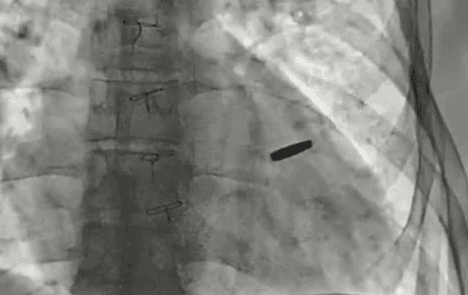

У Києві прооперували захисника «Азовсталі», який три роки провів у російському полоні з кулею у серці